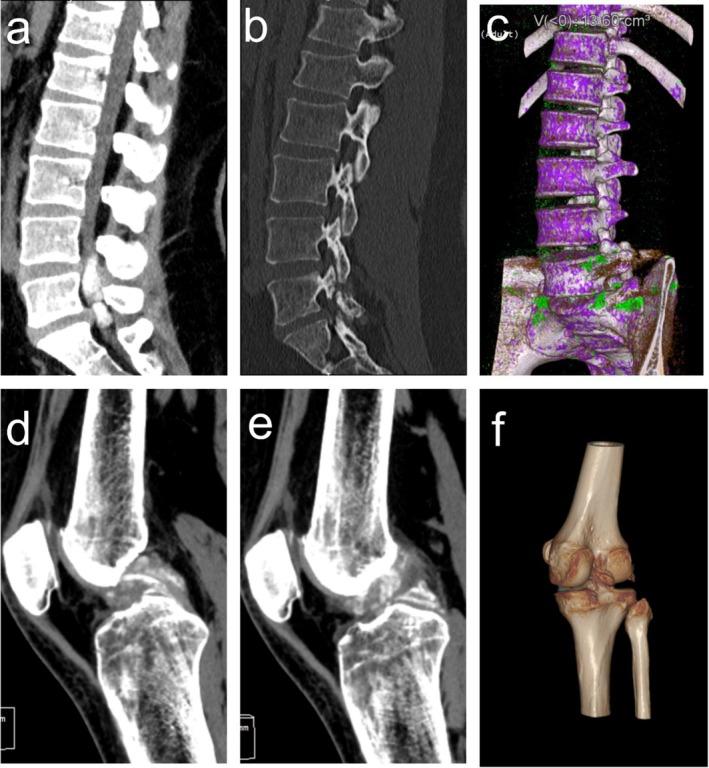

一例成人脊髓内痛风石合并膝关节受累的罕见病例报告。

A Rare Case Report of an Adult With Intraspinal Gouty Stones and Concurrent Knee Joint Involvement.

This case highlights the importance of considering spinal gout in patients with hyperuricemia presenting with atypical back pain or neurological symptoms. Multidisciplinary surgical management, including decompression and joint arthroscopy, combined with urate-lowering therapy and lifestyle modifications, can achieve significant symptom relief and prevent disease recurrence.